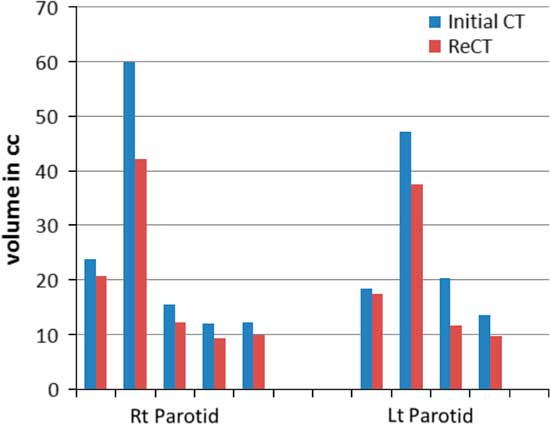

Re-scanning and re-planning at 20th fraction of the treatment shows 27% (13–42%) reduction in parotid volumes (Figure 2), and therefore 21% (7–35%) increase in parotid mean doses. Initial plan calculated on ReCT and CBCT found 15% (9–26%) increase in planning risk volume (PRV) spine maximum doses, which were reduced by re-planning on ReCT. The body maximum doses increased by 6·5% (4–8%) in four patients and 22% in one patient when initial CT plan was calculated on ReCT and CBCT. These results showed a statistically significant difference in the parotids, PRV spine and skin doses with a p-value of 0·01, 0·007 and 0·02, respectively. Figure 3 is the graphical representation of mean doses of parotids and maximum doses of PRV spine and skin in all three plans (initial CT plan, initial plan calculated on ReCT and CBCT).

Figure 2 Parotid volume graphs from initial CT to ReCT in all five patients.